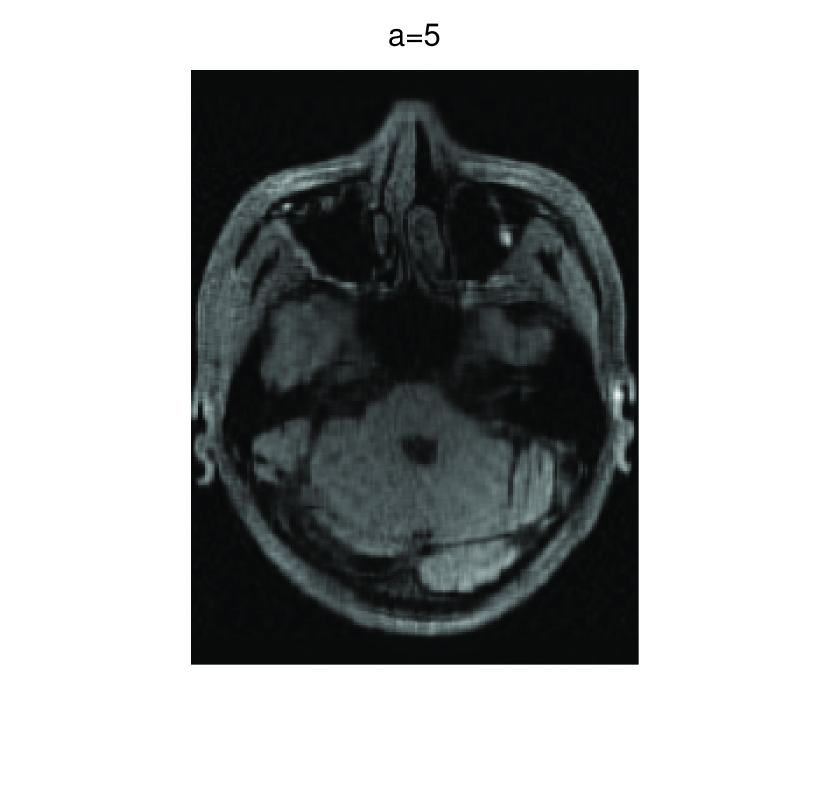

In this subsection, we demonstrate performances of ISVTA on image inpainting problems. The ISVTA is tested on some medical grace images (255×192255192255\times 192 Brain angiography image (BAI), 395×549395549395\times 549 Hand angiography image (HAI) and 419×400419400419\times 400 Intracranial venous image (IVI)). We use the SVD to obtain their approximated low-rank images with rank r=30,40,30𝑟304030r=30,40,30, respectively. Numerical results of ISVTA for theses low-rank image inpainting problems are reported in Table 5, 6, 7, 8.

Refer to caption

Figure 5: Original 419×400419400419\times 400 IVI and its approximation with rank 30.